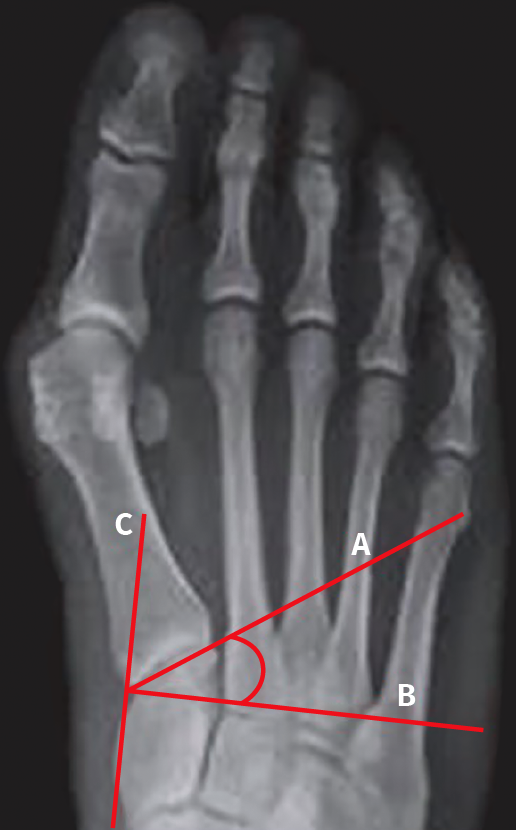

En la actualidad, el paradigma de la tridimensionalidad de la deformidad promulgado por Dayton et al. nos acerca a comprender muchos de esos interrogantes, aunque quedan muchos por resolver.

Creemos que la primera articulación tarsometatarsiana (1.ª ATMT) desempeña un papel importante en la génesis de la deformidad y es el lugar indicado para la corrección del hallux valgus cuando esté presente una rotación del primer metatarsiano (M1).